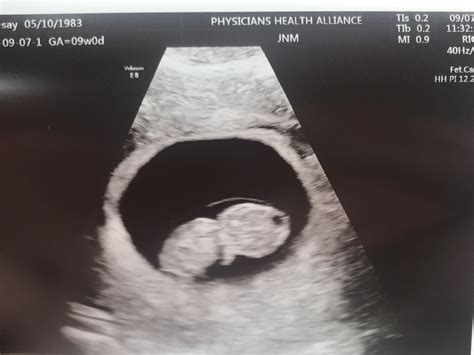

Pregnancy is an exciting journey filled with milestones, and one of the most anticipated moments is the 8 week sonogram. This ultrasound scan provides crucial insights into the development of the fetus and the overall health of the pregnancy. Understanding what to expect during an 8 week sonogram can help alleviate anxiety and prepare expectant parents for this important check-up.

An 8 week sonogram is an ultrasound examination performed around the eighth week of pregnancy. This non-invasive procedure uses high-frequency sound waves to create images of the fetus and the uterus. The primary goal of an 8 week sonogram is to confirm the pregnancy, determine the gestational age, and assess the fetus’s development.

What Can Be Seen on an 8 Week Sonogram?

At 8 weeks, the fetus is still very small, but several key structures can be visualized:

• Embryo: The developing fetus, which is about the size of a raspberry at this stage.

• Heartbeat: The fetal heartbeat is usually detectable and can be seen as a rapid flickering on the ultrasound screen.

• Multiple Pregnancies: If there is a possibility of carrying multiples, the ultrasound can help confirm the number of fetuses.